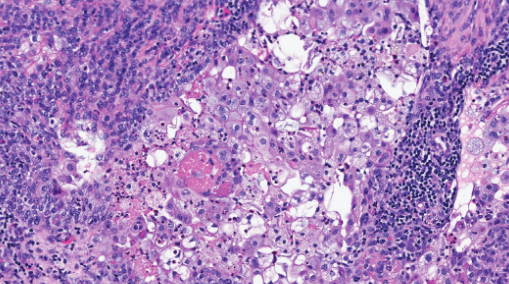

Χρώση αιματοξυλίνης-ηωσίνης. Στιβάδες/πλάκες και οζίδια διηθητικών βασαλοειδών βλαστικών κυττάρων, με περιοχές πλακώδους διαφοροποίησης, νέκρωσης και εστιακά ουδετεροφιλικά μικροαποστήματα (Ευγενική παραχώρηση Dr. V. Penopoulos)